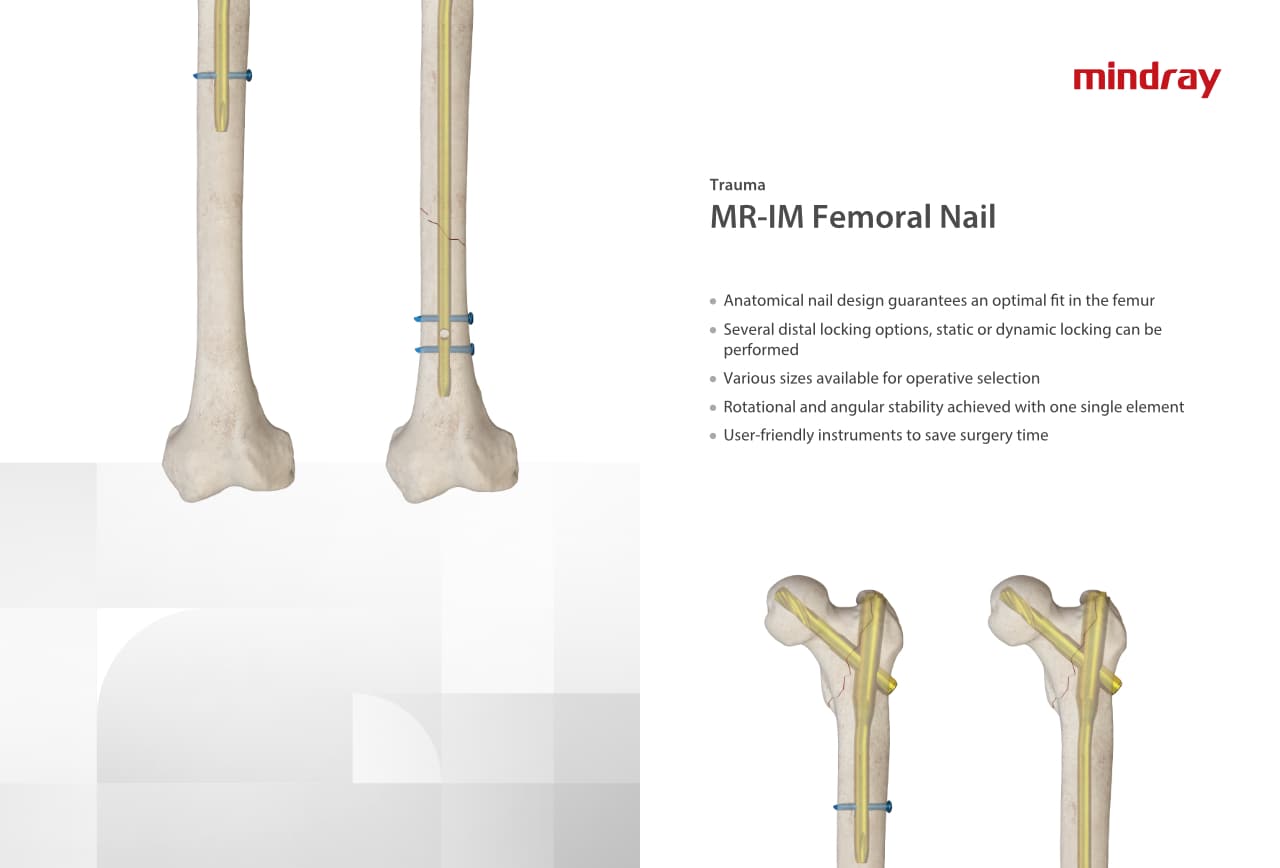

РһСҖСӮРҫРҝРөРҙРёСҮРөСҒРәРҫРө РҝРҫРҙСҖазРҙРөР»РөРҪРёРө РәРҫРјРҝР°РҪРёРё Mindray, СҖР°СҒРҝРҫР»РҫР¶РөРҪРҪРҫРө РІ РЈС…Р°РҪРө, СҸРІР»СҸРөСӮСҒСҸ РҫРҙРҪРёРј РёР· РІРөРҙСғСүРёС… РҝСҖРҫРёР·РІРҫРҙРёСӮРөР»РөР№ РҫСҖСӮРҫРҝРөРҙРёСҮРөСҒРәРҫР№ РҝСҖРҫРҙСғРәСҶРёРё РёР· РҡРёСӮР°СҸ. РһРҪРҫ Р·Р°РҪРёРјР°РөСӮСҒСҸ РёСҒСҒР»РөРҙРҫРІР°РҪРёСҸРјРё Рё СҖазСҖР°РұРҫСӮРәРҫР№, РҝСҖРҫРёР·РІРҫРҙСҒСӮРІРҫРј Рё РјР°СҖРәРөСӮРёРҪРіРҫРј СӮСҖавмаСӮРҫР»РҫРіРёСҮРөСҒРәРёС… Рё СҒРҝРёРҪалСҢРҪСӢС… РёР·РҙРөлий, РҝСҖРҫРҙСғРәСҶРёРё РҙР»СҸ Р°СҖСӮСҖРҫРҝлаСҒСӮРёРәРё Рё РҙСҖСғРіРёС… С…РёСҖСғСҖРіРёСҮРөСҒРәРёС… РёР·РҙРөлий. РЎ РјРҫРјРөРҪСӮР° СҒРІРҫРөРіРҫ РҫСҒРҪРҫРІР°РҪРёСҸ РІ 1999 РіРҫРҙСғ РјСӢ СғСҒРҝРөСҲРҪРҫ РҝСҖРҫСҲли СҒРөСҖСӮифиРәР°СҶРёСҺ ISO 9001, ISO 13485 Рё CE, РІСӢРҙР°РҪРҪСғСҺ T?V Рё СҚРәСҒРҝРҫСҖСӮРёСҖСғРөРј РҝСҖРҫРҙСғРәСҶРёСҺ РІ РұРҫР»РөРө СҮРөРј 50 СҒСӮСҖР°РҪ РҝРҫ РІСҒРөРјСғ РјРёСҖСғ.